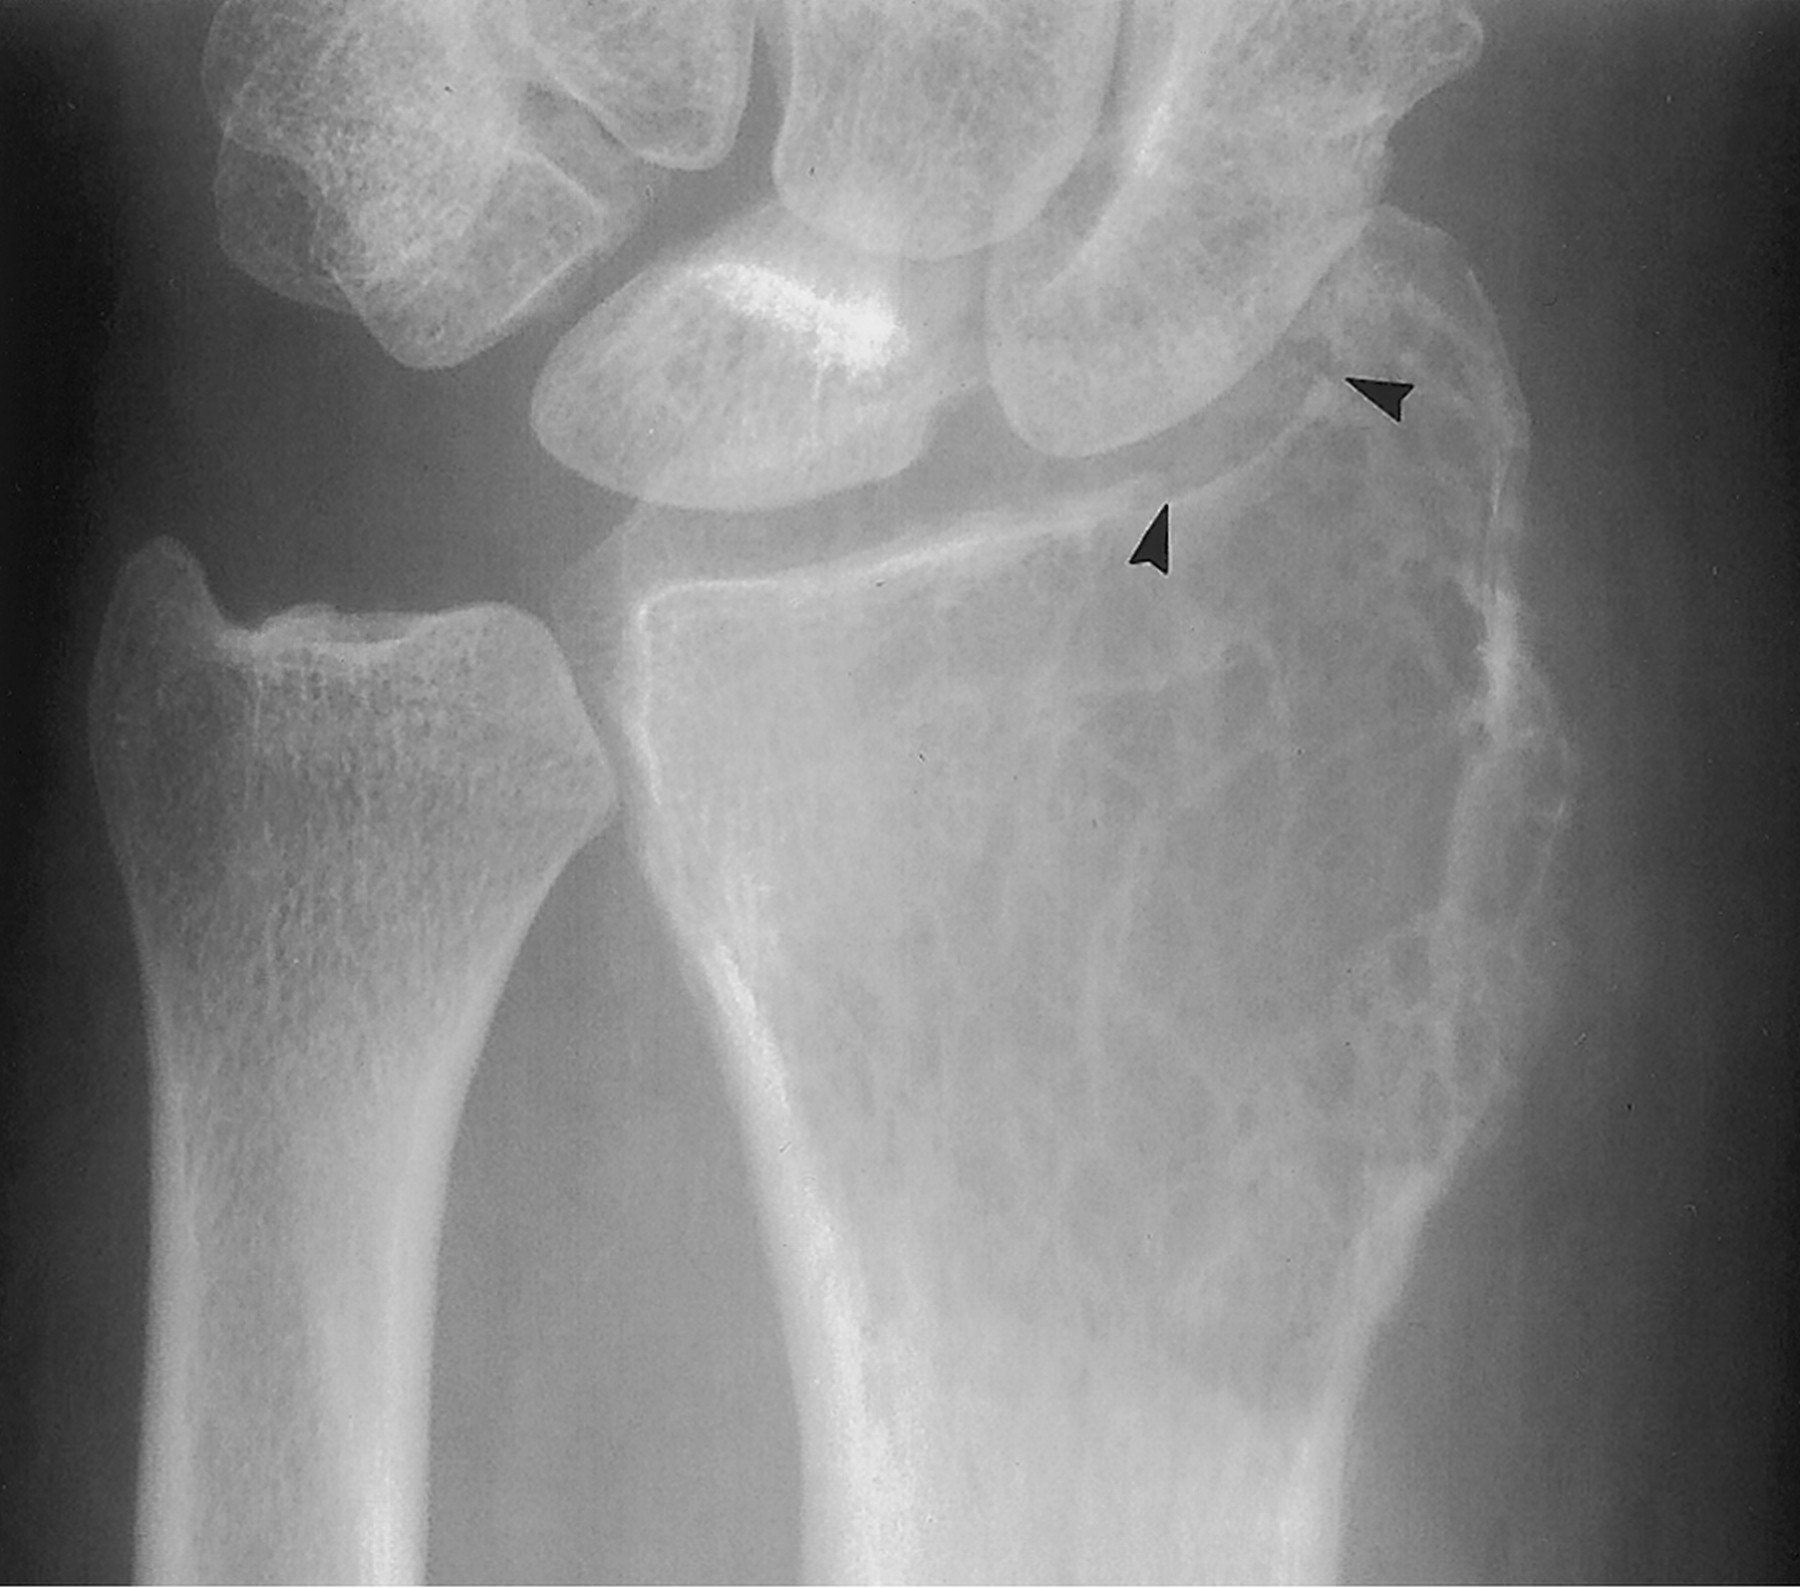

Гигантоклеточная опухоль.

Злокачественная гигантоклеточная  опухоль возникает из доброкачественной (частота 10-20%). После операции возможно появление рецидива опухоли.